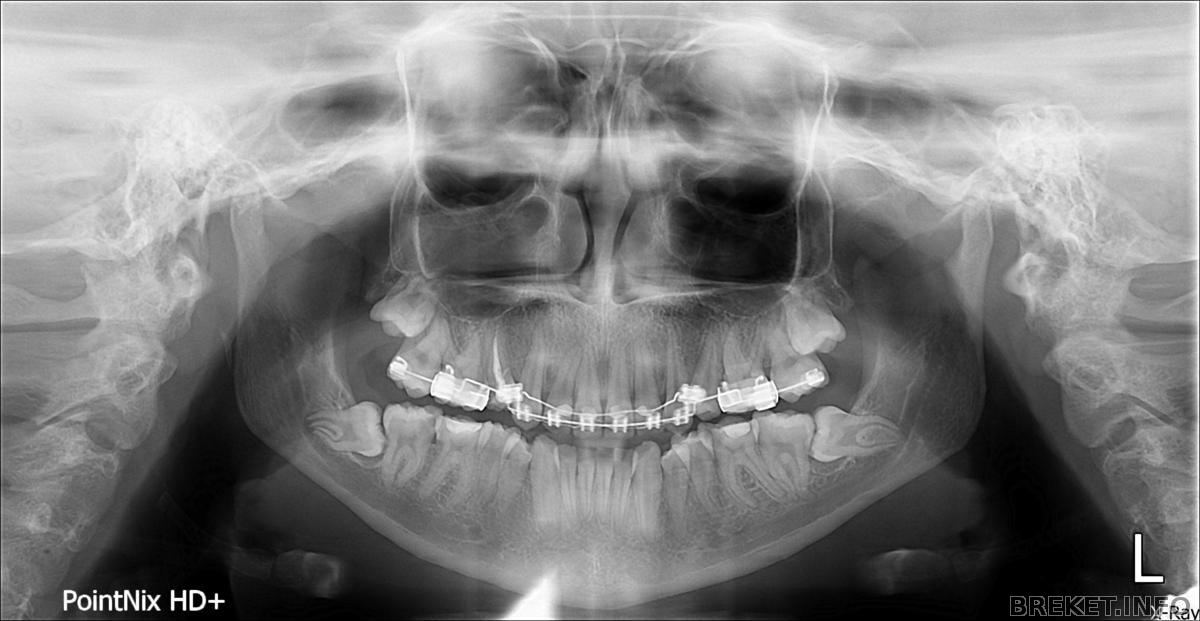

Сходила я сегодня и сделала снимок,потом пошла к доктору,который мне лечил этот зуб. Она сказала,что корень сместился,надо ехать со снимком к ортодонту,снимать кольцо,а потом к ней лечить(пломбировать) каналы)))

Снимок старый,мне уже удалили 2 зуба на нч и поставили брекеты

По поводу снимка - верхние восьмерки опасные. Куда орт смотрит?!

Да кстати насчет больного зуба - там на пятерке рядом была киста еще в момент снимка. Плюс перфорация пульпарной камеры на самой шестерке, видно уходящий вперед и вверх кариозный канал. И вообще - в бесплатной сказали депульпировать, а в платной просто запломбировали. Странно это все. Совковые врачи, бессмысленные и беспощадные, один поставил брекеты не удалив растущих проблемных восьмерок и не подключив семерки, другой заклеил перфорированную пульпу, так и до гангрены недалеко.